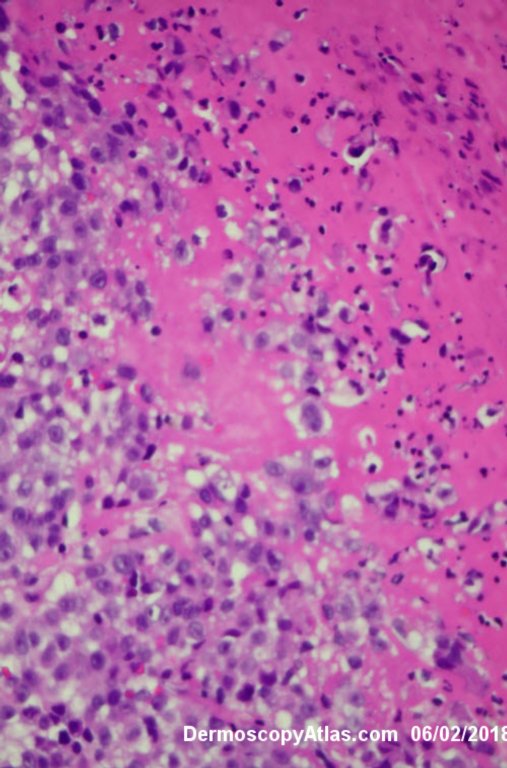

Site: Leg

Diagnosis: Melanoma invasive

Lady in her early 80s who presented with this lesion on her ankle. The pigmented area had been there for some time but the pink area was bleeding and new. Shave of surrounding area and a punch biopsy of the new pink area showed mainly surrounding in situ melanoma with invasive melanoma in the pink area 1.8 mm thick. Having a 2cms margin excision of the whole area and a graft.